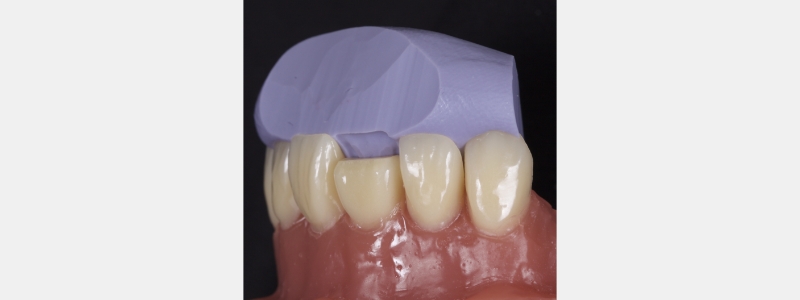

I prefer a PVS putty, which is high contrast in color. For example, blue, green, or purple rather than beige or pink. PVS putty improves visualization when placing the initial composite shell.

When fabricating the stent, it will often extend onto the facial surface, resulting in access issues when layering. Instead, trim the stent with a sharp blade such as an 11 scalpel or a simple carpet knife. The trim should be through the incisal edge midway between the facial and palatal surfaces. The trim angle should mirror the tooth’s incisal-facial surface to be restored.